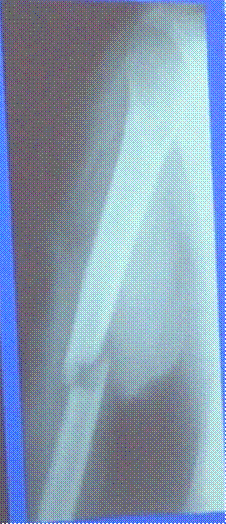

Винтообразный перелом диафиза большеберцовой кости со смещением Нарушение непрерывности кортикального слоя на границе средней и нижней трети диафиза, линия просветления идет в виде треугольников через весь поперечник кости, имеется смещение по ширине, длине и под углом кзади и кнаружи и равным 160 градусам.